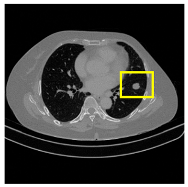

3.4.2. Representative Cases with Segmentation Challenges on the MEF-PN35 Dataset

To complement the quantitative evaluation, we present a set of representative cases from the clinical dataset that exhibited typical segmentation challenges. These cases were selected to reflect diverse morphological characteristics observed in pulmonary nodules, such as spiculated boundaries, small size, vessel adherence, pleural attachment, cavitation, and clear isolation. Rather than aiming for exhaustive categorization, our intent is to highlight a range of practical difficulties encountered in real-world scenarios and to qualitatively assess how different boundary-aware loss functions respond to these variations. Each challenge is labeled (C1) through (C5) in Table 10 and is consistently referenced in the corresponding detailed illustrations that follow.

Following the summary in Table 11, we present detailed visual comparisons for selected representative cases, each corresponding to a specific segmentation challenge. These cases are consistently labeled using the Challenge ID (CID) codes defined in Table 9 to facilitate cross-referencing between the summary and the case illustrations. Each table reports segmentation results across three loss configurations (Sobel, Laplacian, and Hausdorff) using five columns. Loss indicates the boundary loss formulation applied in each case, where Dice loss is combined with a boundary term computed using Sobel, Laplacian, or Hausdorff operators. The Segmentation Result column shows four images side by side: the input CT patch, the manual ground truth, the model prediction, and a color-coded difference map between ground truth and prediction. In this map, green indicates true positives, blue represents true negatives, red corresponds to false positives, and yellow denotes false negatives. The final column, Attention Map, presents Grad-CAM visualizations derived from one of the Adaptive Attention Fusion (AAF) layers in the encoder path. These maps illustrate the spatial focus of the model, with red/yellow regions indicating strong attention and lighter or neutral tones indicating lower activation. All six cases are presented in detail in Table 11, Table 12 and Table 13, providing a comprehensive qualitative analysis of how each loss configuration performs under specific segmentation challenges observed in real clinical data.